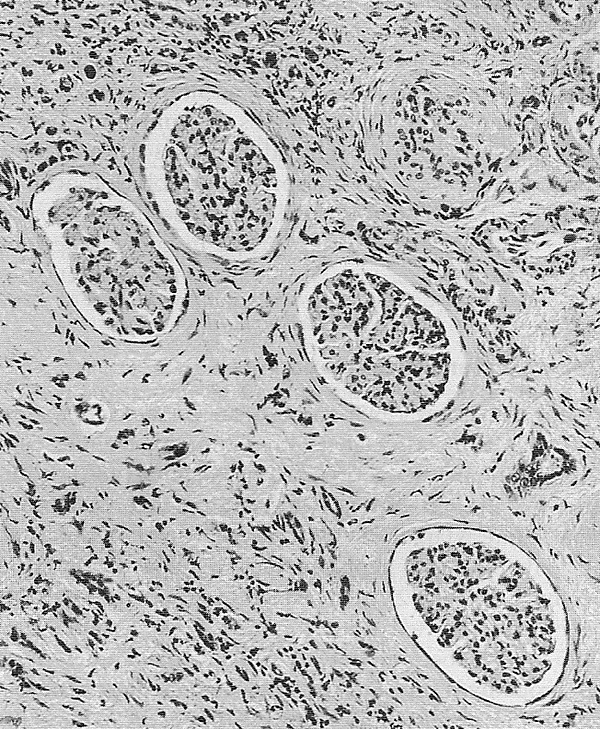

Основным патогенетическим механизмом БЭН считается хроническое воздействие аристолоховой кислоты, содержащейся в семенах растения Aristolochia clematitis, которые случайно попадают в зерновые культуры в эндемичных районах. После метаболизма в организме это вещество вызвывает характерные генетические мутации и приводит к повреждению почечных канальцев. Данный процесс провоцирует прогрессирующий интерстициальный фиброз с атрофией канальцев и склерозом клубочков[2].

БЭН характеризуется прогрессирующими патологическими изменениями в почках, которые развиваются поэтапно. На ранней стадии заболевания поражаются преимущественно наружные отделы коркового слоя, где наблюдается расширение мезангия клубочков и утолщение их базальных мембран, сопровождающееся дистрофическими процессами в проксимальных канальцах[4].

По мере прогрессирования болезни патологические изменения становятся более выраженными. В субклинической стадии продолжается утолщение базальных мембран, причём в дистальных канальцах этот процесс менее интенсивен, чем в проксимальных. Одновременно развивается начальный интерстициальный склероз и появляются характерные сосудистые изменения — утолщение стенок артериол с неравномерным сужением их просвета[4].

В терминальной стадии происходит резкое уменьшение размеров почек (их масса может снижаться до 40 грамм при норме 115—170 грамм). Структура почечной ткани значительно изменяется: большинство канальцев коркового вещества полностью атрофируются, теряя эпителиальную выстилку, а повреждённые клубочки и канальцы замещаются соединительной тканью. Эти необратимые изменения приводят к полной утрате функциональной активности поражённых почек[4].

Биопсия почки с гистологическим исследованием биоптата выявляет характерные морфологические изменения[2].